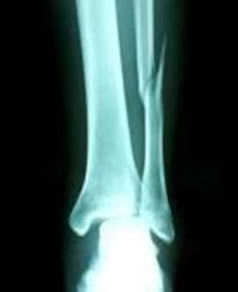

下腿骨骨折(脛骨骨折、腓骨骨折)の基礎知識 point 下腿骨骨折(脛骨骨折、腓骨骨折)とは すねの骨は脛骨と腓骨の2本からなりますが、下腿骨骨折はそのうち一方または両方が骨折することで、交通事故やスポーツ、転倒が原因で起こることが多いです。 今回は、骨折がどれくらいでくっつくのか、どのようにして治るのかを簡単に説明します。 参考にしてみてください。 骨折の癒合日数 骨折した部位によって、骨癒合の期間は異なります。 部位だけでなく、患者の年齢、栄養状態、全身状態、治療法なども影響します。 ツイート 8月31日 (月)のトレーニングで石川俊輝選手が負傷し、9月1日 (火)にさいたま市内の病院にて手術を行いましたので、お知らせいたします。 石川俊輝 選手 (MF5) 診断結果:右足腓骨骨折 全治:3カ月 生年月日:1991年7月10日 (29歳) シーズン記録

あくまで目安ですが、腓骨骨折のみのケースだと 全治 (骨癒合)までおよそ 6週間 前後かかります。骨折が治りました! ちなみに全治と完治の違いってご存じですか? 今日、病院に行ってきました! 10時30分の予約でしたが、9時58分受付終了。 その足で、CT検査受付口に。 「入り口で待っていて下さい! 」 との声で、入り口前の廊下に移動すると 交通事故の被害に遭い、脛骨骨折や腓骨骨折の怪我を。 その後、もしも後遺症が残ってしまったとしたら。 これからも長く続く治療やリハビリの生活では、 脛骨骨折・腓骨骨折から回復するために支払う治療費 怪我をしたことや後遺症が残ったことによる精神的苦痛に対する慰謝料